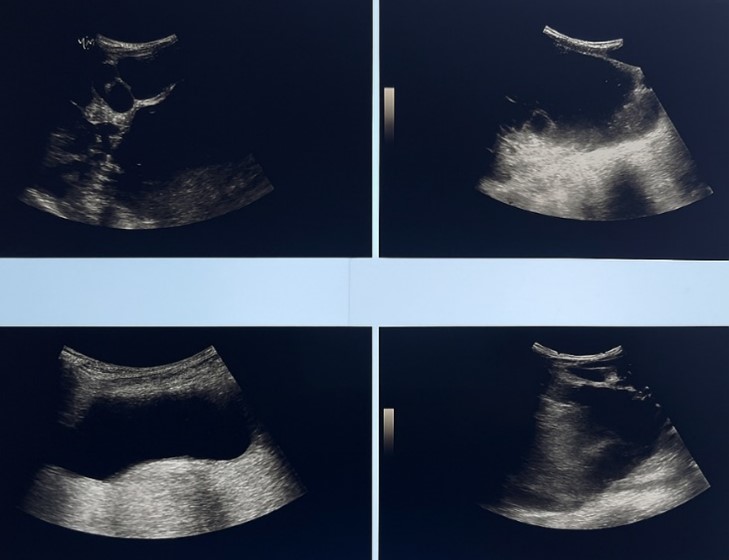

Complementary ultrasound confirmed that these cysts had thin walls. Some contained finely echogenic material, and others had internal septations.

The kidneys were of normal size, with regular contours and good vascular nephrography. Multiple bilateral renal cysts were observed, the largest being located at the lower pole of the right kidney, measuring 24 mm in diameter, with a simple appearance, classified as Bosniak I.

On conclusion, the imaging features of both hepatic and renal cystic involvement are highly suggestive of hepatorenal polycystic disease, with the presence of a large compressive hepatic cyst.

Figure 3: ultrasound images showinga multiple hepatic cysts containing finely echogenic material, and others had internal septations.